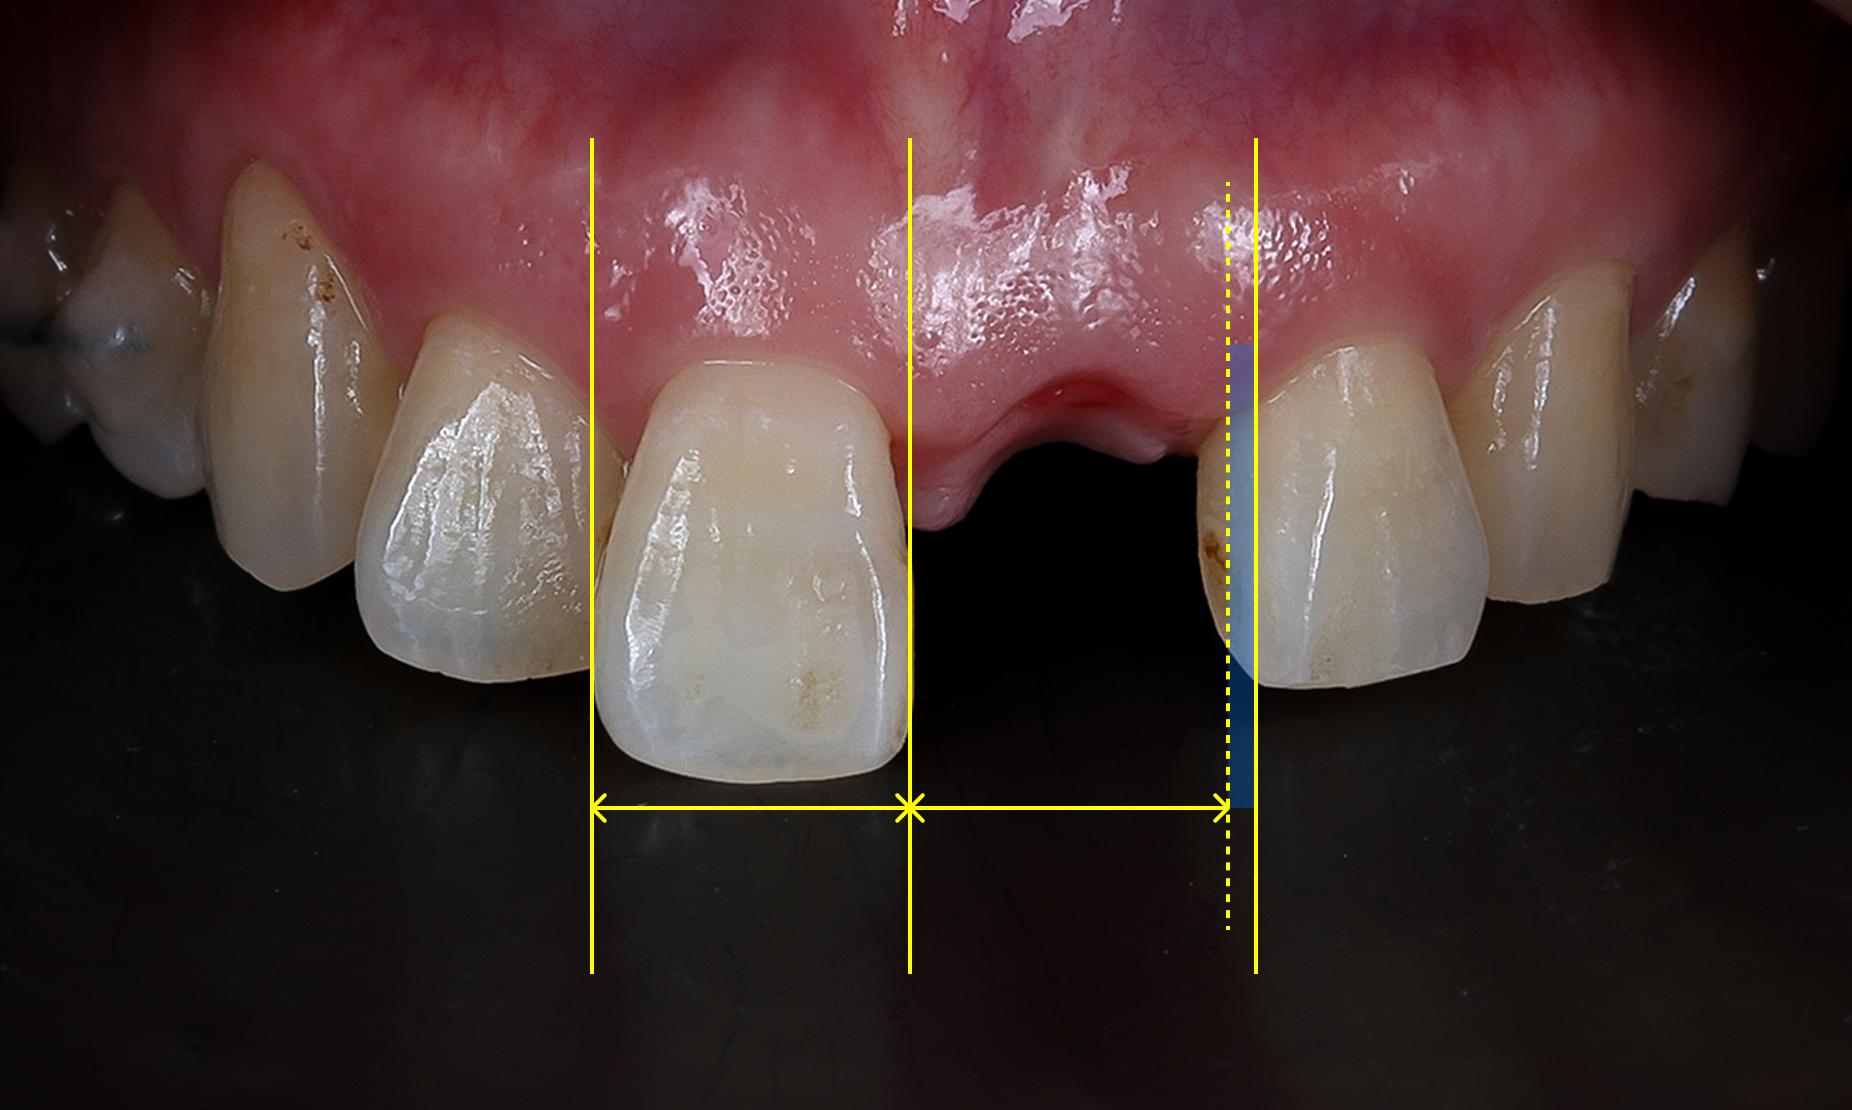

初診時のお口の状態を確認したところ、左右の前歯のスペースが揃っていないことが判明しました。このままでは左側のインプラントを挿入すると不自然に大きな歯となり、審美性が損なわれるリスクがありました。

そこで当院の「逆算シミュレーション」に基づき、最終的な美しい仕上がりを目指して治療計画を立案しました。具体的には以下の方法を採用しました

- 左側の隣接歯の幅をダイレクトボンディングで補い左右対称に調整

- 右側の欠損部位にはインプラントを用いて補綴(ほてつ)

(模型上でブルーの部分が診断用シミュレーション)